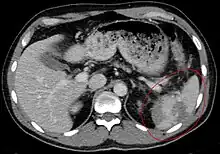

Traumatic rupture of the spleen on contrast enhanced axial CT (portal venous phase)

Splenic rupture is usually evaluated by FAST ultrasound of the abdomen.[5] Generally this is not specific to splenic injury; however, it is useful to determine the presence of free floating blood in the peritoneum.[5] A diagnostic peritoneal lavage, while not ideal, may be used to evaluate the presence of internal bleeding a person who is hemodynamically unstable.[6] The FAST exam typically serves to evaluate the need to perform a CT scan.[6] Computed tomography with IV contrast is the preferred imaging study as it can provide high quality images of the full peritoneal cavity.[5]